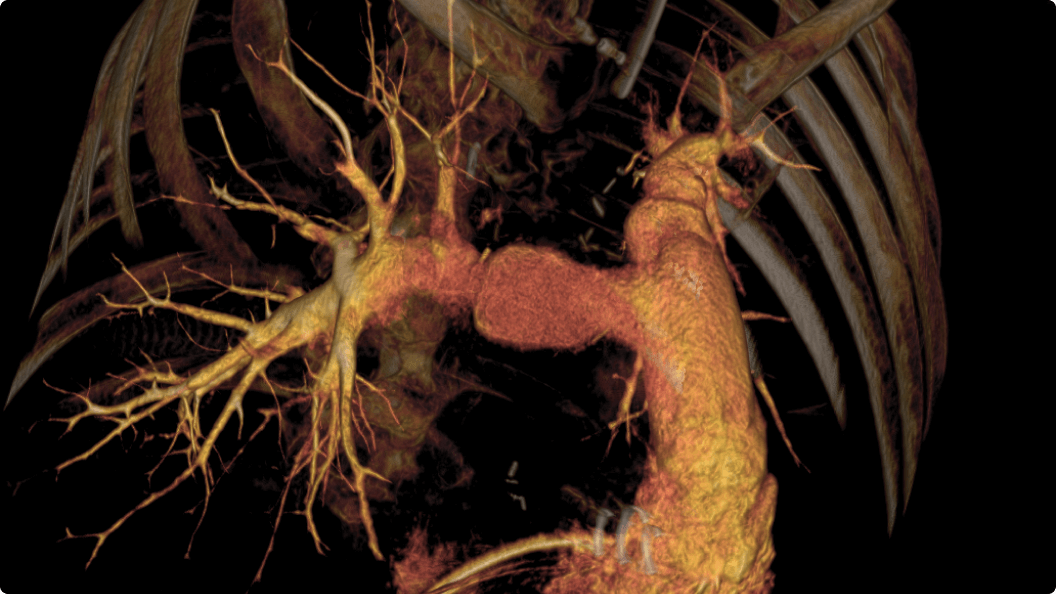

3D CT HD5

Optimierung von Diagnosen, chirurgischen Planungen, interventionellen Verfahren und Nachfolgeuntersuchungen

3D CT HD5 ist eine Option, die auf fortschrittlichen Algorithmen basiert. Diese Algorithmen verbessern die Visualisierung von Weichgewebe, reduzieren Rauschen und minimieren Artefakte, die den Visualisierungskomfort beeinträchtigen können. 3D CT HD bietet eine qualitativ hochwertige Bildgebung von internen Körperstrukturen einschließlich Gefäßen, Knochen und Weichgewebe. Mit dieser Funktion können Ärzte auf Aufnahmen von hoher Qualität zugreifen und fundierte Entscheidungen treffen.

3D CT HD5: Enhanced soft-tissue visualization and noise reduction for high-quality CBCT imaging